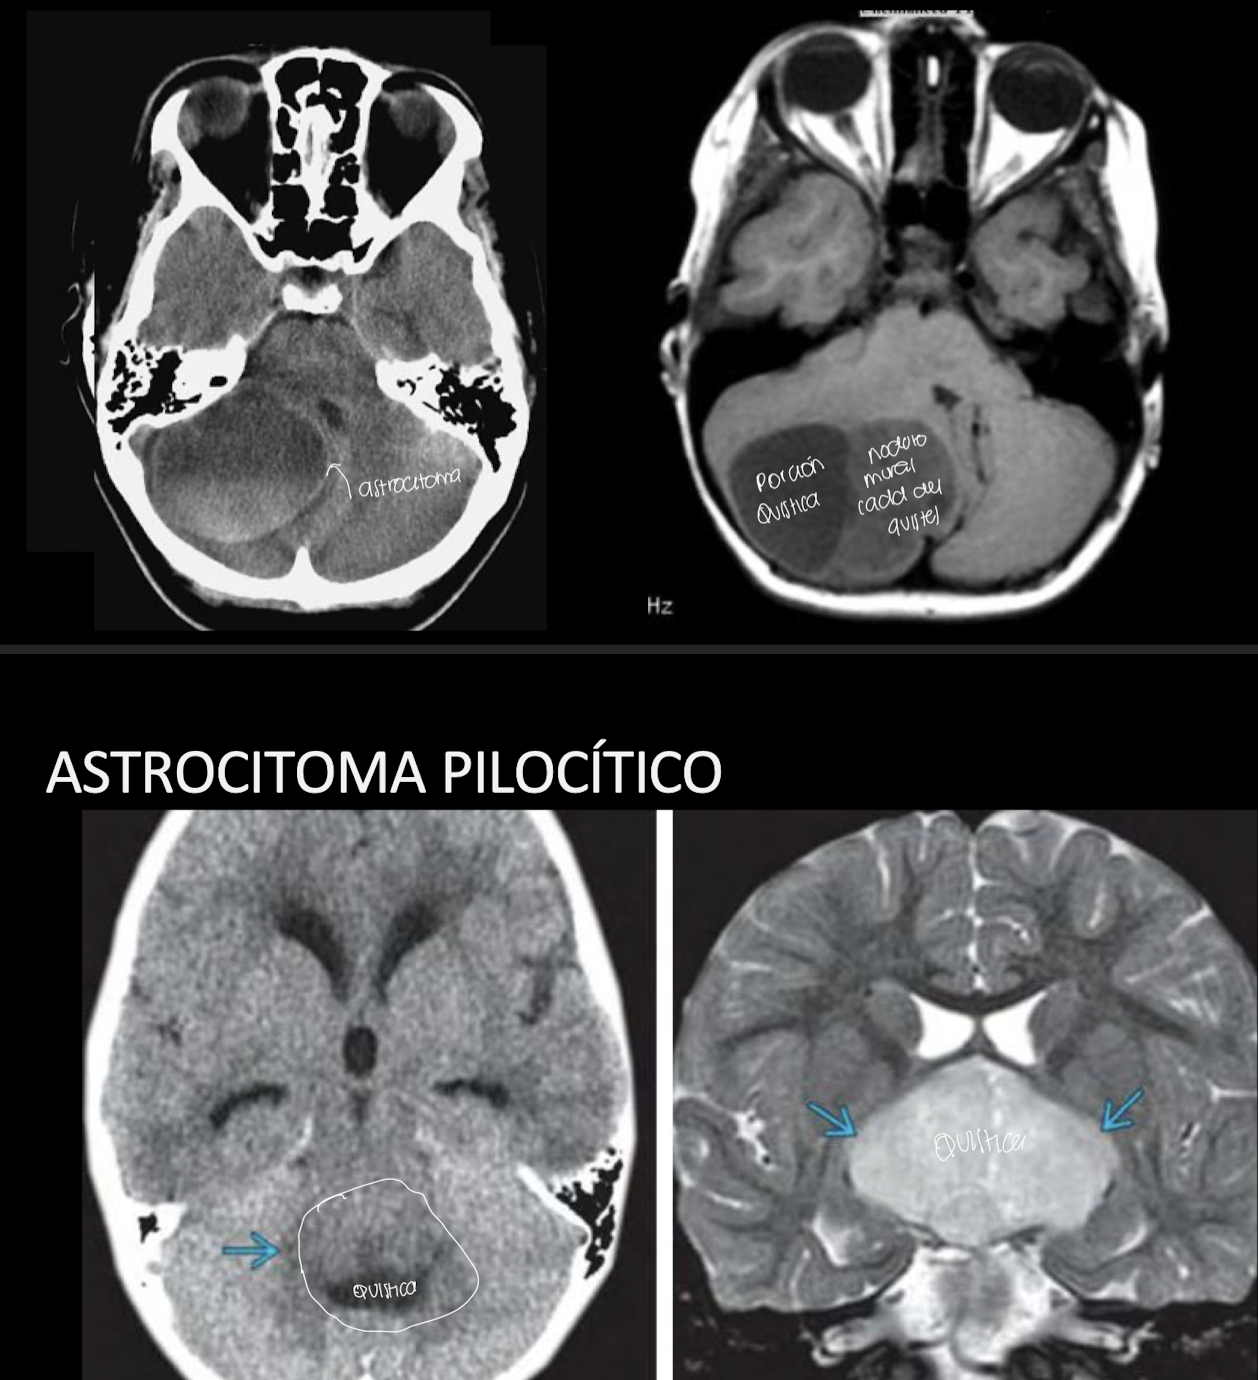

Astrocitoma pilocítico

Características y def

Grado1 OMS: beningo

Lesion quistica nodulo mural

Adultos jovenes, primeras dos decadas de la vida y niños

Imagenología y su mejor característica AP

RM: masa cerebelosa nodulo mural

Nervio optico, quiasma y tracto agrandado

Localizción AP

60% cerebelo

25-30% N. optico